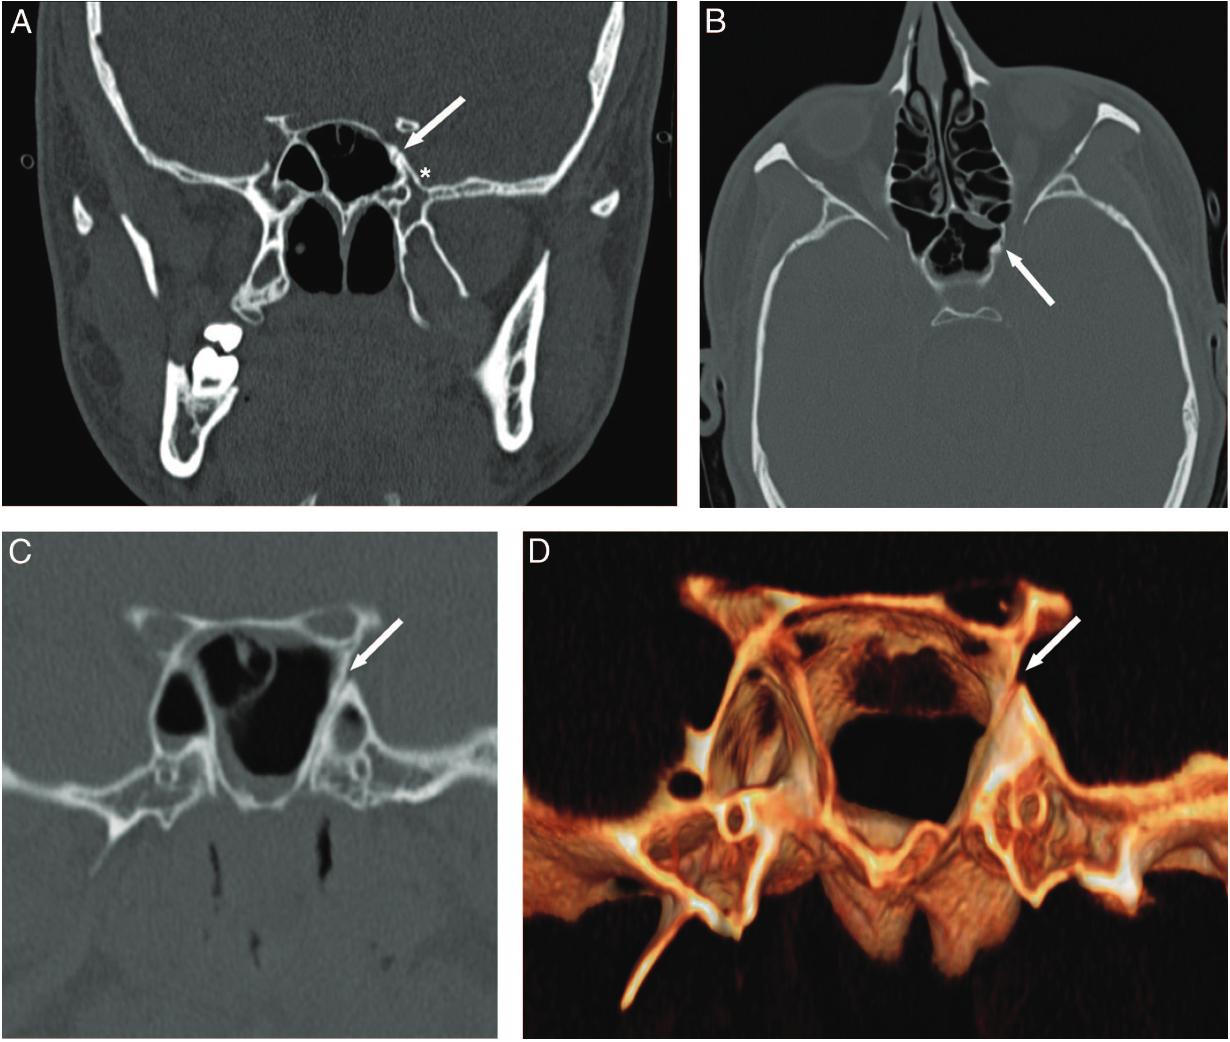

Darstellung eines Patienten mit einem Sternberg Kanal in der CT Bildgebung. Abbildung adaptiert von 1. Barañano CF, Cure J, Palmer JN, Woodworth BA. Sternbergs Canal: Fact or Fiction? American Journal of Rhinology and Allergy. 2009;23(2):167-171. doi:10.2500/ajra.2009.23.3290